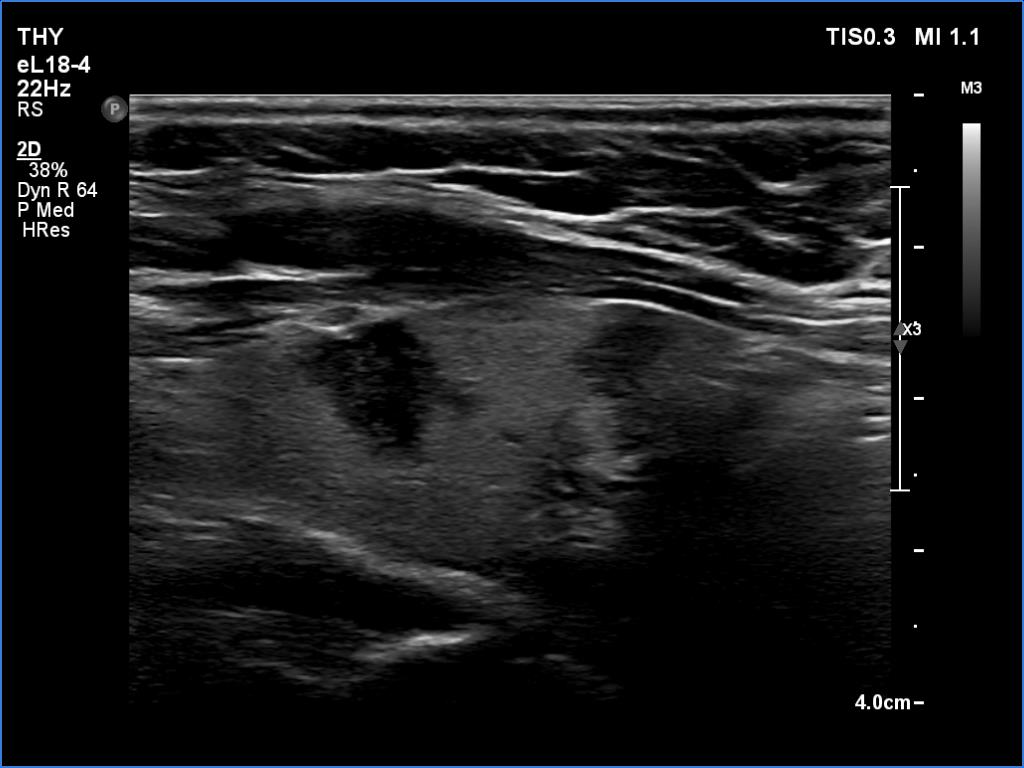

First examination (first and second rows of images):

Clinical data: A 37-year-old woman requested a screening. Recently, her mother was diagnosed with hypothyroidism and we suggested to screen the first-degree female relatives for autoimmune thyroid disease.

Palpation: no abnormality.

Laboratory tests: TSH 8.79 mIU/L, aTPO 808 U/mL.

Ultrasonography. The thyroid was echonormal or minimally hypoechoic and had several discrete, more hypoechoic areas. Two of them in the left lobe were remarkable because of irregular borders and nonparallel orientation.

Cytology was performed from the larger lesion in the left lobe and resulted in Hashimoto's thyroiditis.

Daily 50 microgram levothyroxine was administered. We suggested repeat ultrasound and cytology in a year.